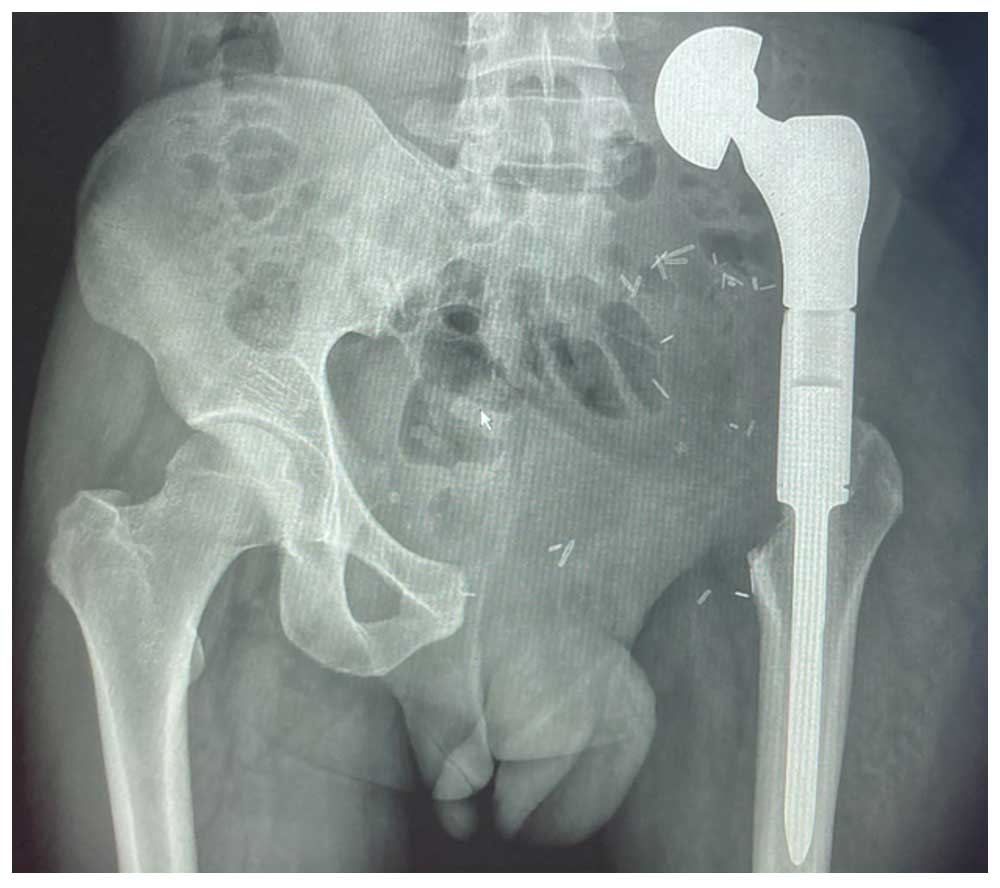

Ameliyat Sonrası: Röntgende internal hemipelvektomi sonrası proksimal femur tümör protezi ile kalça transpozisyon işlemi görülmekte.